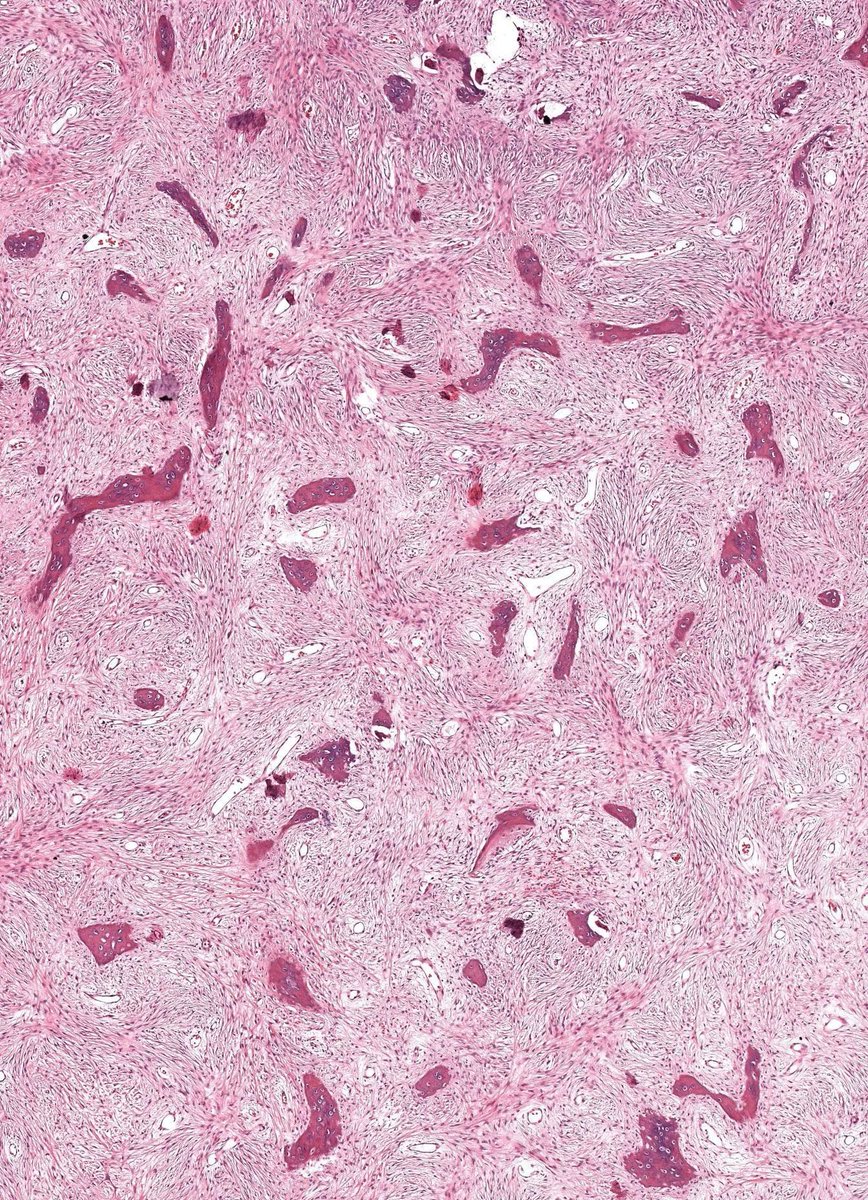

Microscopic (histologic) description

- Branching and anastomosing irregular trabeculae of woven bone ("C" and "S" shapes) with no conspicuous osteoblastic rimming

- No / rare osteoclasts

- Intervening fibrous stroma containing cytologically bland spindle cells, without prominent cytologic atypia

- Mitotic figures rare

- Stromal changes, including myxoid change and fatty metaplasia, may be seen in some cases (BMC Musculoskelet Disord 2003;4:20)

Microscopic (histologic) images